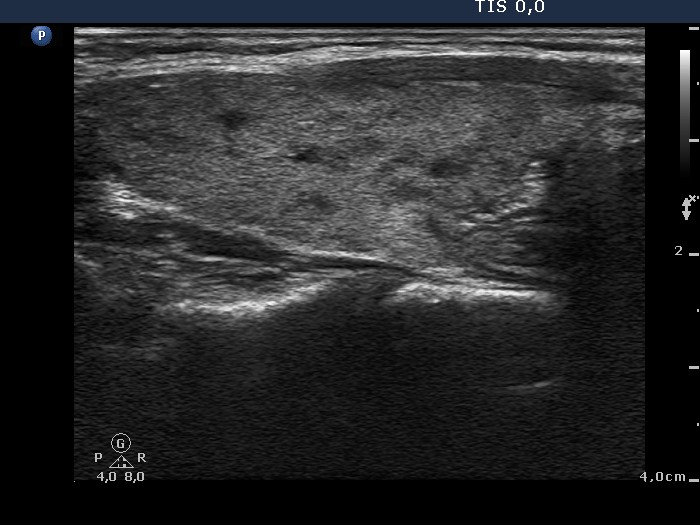

Follow-up investigation 33 months after first visit (ultrasonographic picture 5)

Patient on daily 20 mg methimazole therapy in euthyroid state

Left lobe, longitudinal scan. There are small hypoechogenic areas within the echonormal lobe.